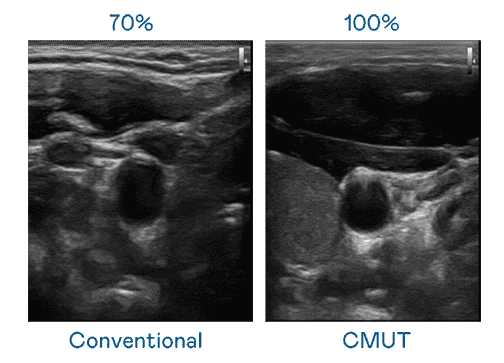

CMUT 技术是一种用电容式微机电元件来产生超音波讯号的技术。。。与传统 PZT 压电式技术相比,,,CMUT 频宽增加 30%,,更宽频的超音波讯号让影像解析度大幅提升,,,是实现高影像品质医疗超音波扫描、、、、促进精准医疗发展的关键技术。。

大频宽带来超清晰影像

超音波影像的解析度高低,,,,首先取决于探头能发出的讯号频宽。。尊龙z6 CMUT 可提供高清晰的超音波讯号,,,,提供高频宽、、、、高灵敏度、、影像纹理细节更高的超音波影像,,,,协助医护人员缩短影像判读时间及利用精准的医疗影像进行诊断。。